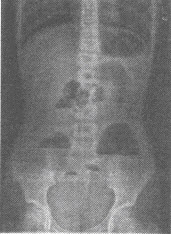

患者,男性,40岁,突发腹痛,腹胀逐渐加重,呈阵发性,查肠鸣音亢进,既往有腹部手术史,如图所示,最可能的诊断为()

A:急性腹膜炎

B:胃肠道穿孔

C:急性胰腺炎

D:小肠急性肠梗阻

E:急性阑尾炎